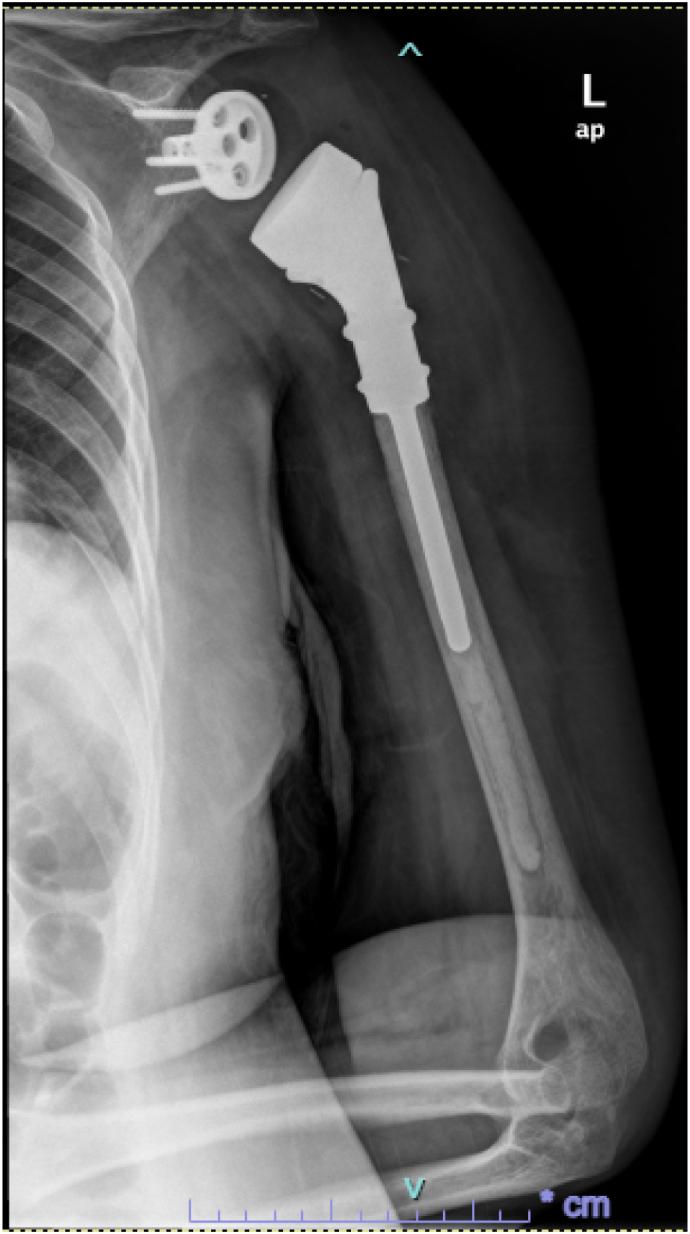

CASE PRESENTATION

We report a rare case of primary bony HS of the proximal humerus without bone marrow involvement in a healthy 33-year-old pregnant woman. She was successfully treated with surgical resection during pregnancy and radiotherapy post-delivery.

我们报告一例罕见的肱骨近端原发性骨HS病例,患者为一名33岁的健康孕妇,无骨髓受累。她在孕期接受了手术切除,并在产后接受了放疗,治疗成功。